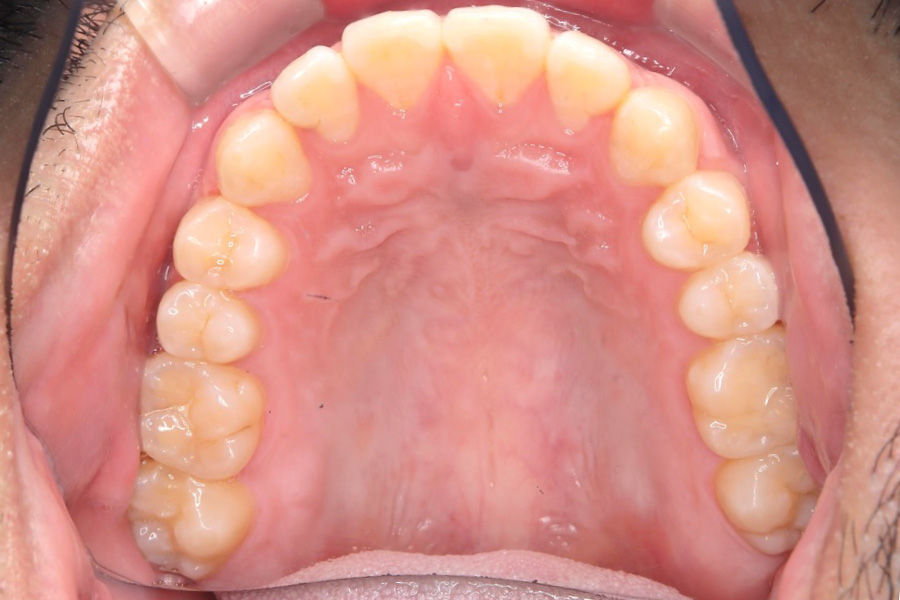

【20代男性】

歯の隙間を

インビザライン矯正で治療したケース

治療後

主訴 歯の隙間が気になる

治療内容 インビザライン矯正

非抜歯

治療に伴うリスク 矯正終了後は、リテーナーを指示通りに使用し、歯の後戻りを防ぐ必要があります。